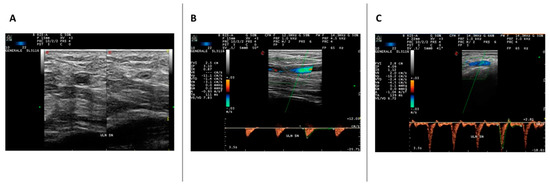

2.1. US Evaluation

4.3. Decision Tree Model, ROC Curve and Clinical Correlation Results